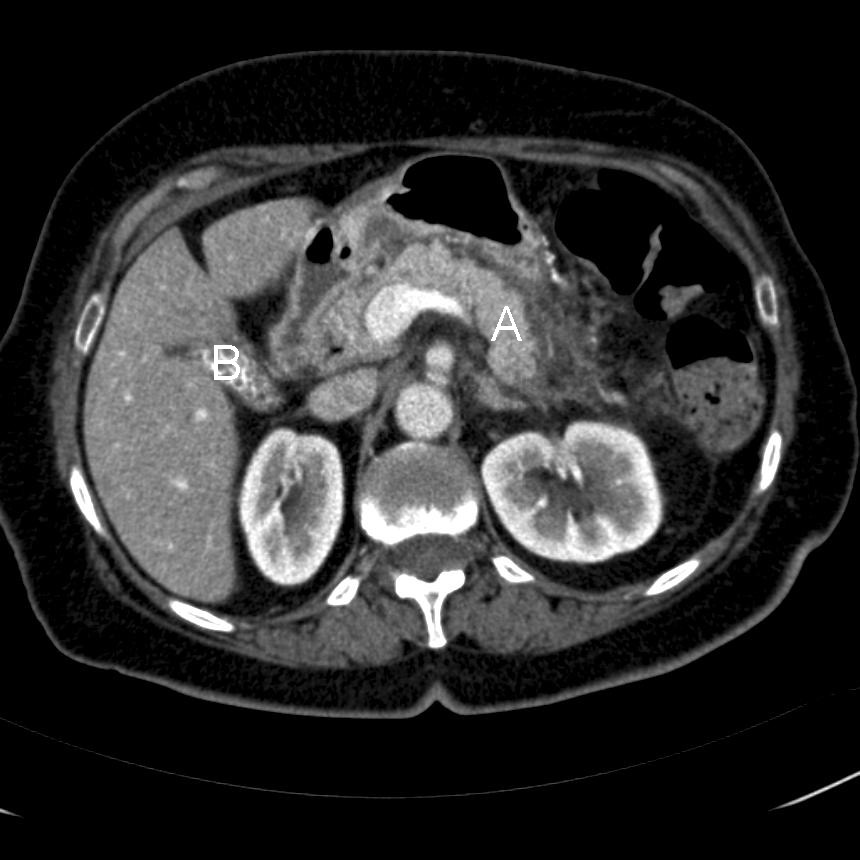

CT-scanning af abdomen viser pankreatit og kolecystit.

• CT (ved mild og svær) pankreatitis vil vise interstitiel pankreas ødem

• Bruges i klinisk alvorlige tilfælde for at vurdere udbredelsen af nekrose, hos patienter som responderer dårligt på behandling eller ved diagnostisk usikkerhed

• Dynamisk CT, dvs. CT med i.v. kontrast, er altid at foretrække og har vist sig værdifuld i udredningen af lokale komplikationer

• Er fundet at have en sensitivitet på 78 % og specificitet på 86 % ved alvorlig akut pankreatitis

• Manglende kontrastopladning indicerer udvikling af pankreasnekroser

• Omfanget af nekroser i pankreas og antallet af peripankreatiske væskeansamlinger kan kvantificeres og anvendes som prognostisk hjælpemiddel